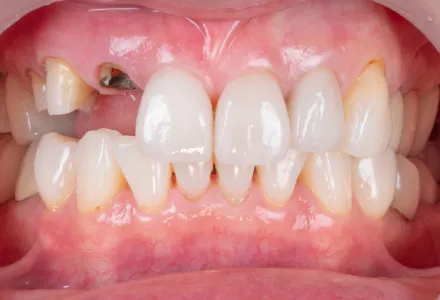

インプラント症例2

Before

After

- 治療名

- インプラント治療+セラミックの詰め物

- 患者さん

- 50代 女性

- 執刀医

- 田中院長

- 治療

内容 - 今回は前歯をインプラントで回復し、隣接する歯にはセラミック詰め物を行いました。インプラントとセラミックを組み合わせることで、噛む機能だけでなく口元全体の調和にも配慮した治療を行いました。患者様から「色や形がとても自然で、治療したことが分からないほどきれいに仕上げていただきました。人前で安心して笑えるようになり、田中院長に治療していただき、人生が変わったように感じています。」とありがたいお言葉をいただきました。

- 治療期間

- 4ヶ月

- 治療費

- 1,100,000円〜

- リスク

- 適切なメンテナンスが行われない場合、周囲の歯ぐきに炎症が起こり、インプラントの安定性に影響することがあります(インプラント周囲炎)。

セラミックは強い衝撃や歯ぎしりなどにより、欠けたり割れたりすることがあります。